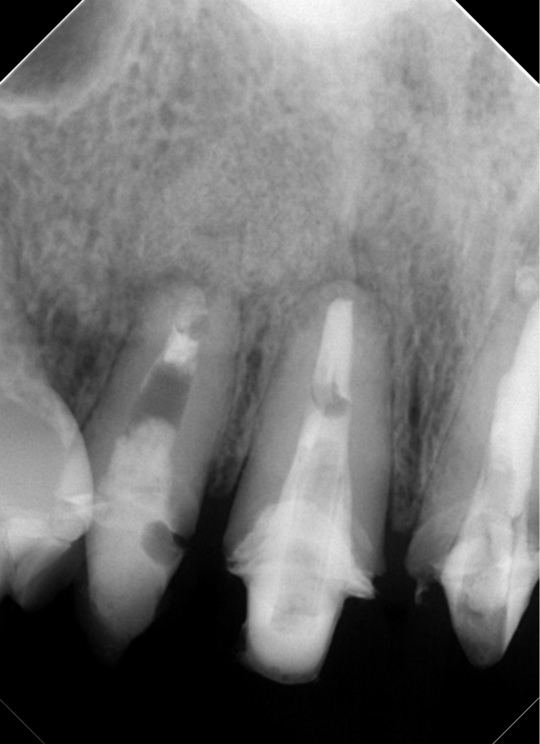

自費根管治療症例1 治療前

左上の奥歯の腫れと噛んだ時の痛みで来院。

根の先にうみが溜まっています

副鼻腔の骨の壁を突き破っています